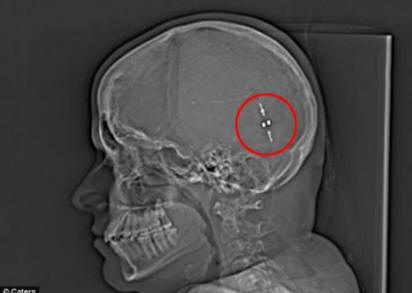

De miután megtaláltak egy módszert a felesleges folyadék eltávolítására az agyát a gyomrába, élete megváltozott. Csatorna, más néven gasztroperitoneális sönt, az agyat és a gyomort összekapcsolva, lehetővé téve azt emésztjük az agy folyadékát és csökkentjük az agyra nehezedő nyomást.

És csak tavaly májusban kaptak egy lányt šuntiért a fölösleges folyadék elvezetése. Sam azonnali megkönnyebbülést remélte, de az agyának időbe telt, hogy hozzászokjon egy idegen testhez. Egy idő után Sam agya azóta adaptálódott a változáshoz akkor ismét normális életet él. Az élet ideje